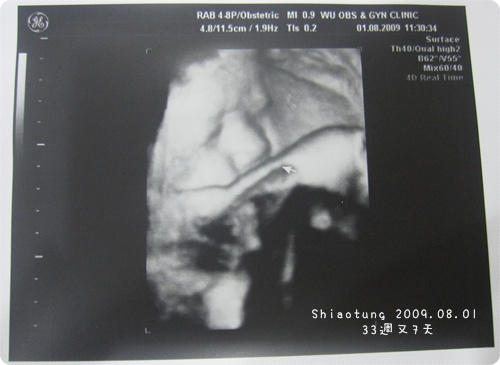

後來看了超音波照片...

原來大小姐頭就頂在我膀胱!

不偏不倚...我想是當枕頭吧?行行好,就不能乖乖倒立就好嗎?

臉也是遮到一點...

但是醫生一看就說:這臉有嘟喔!

他看看靓靓又看Lilyan說:快比姐姐的臉還肉。

後來還有傾斜更側面的肉臉給我看...